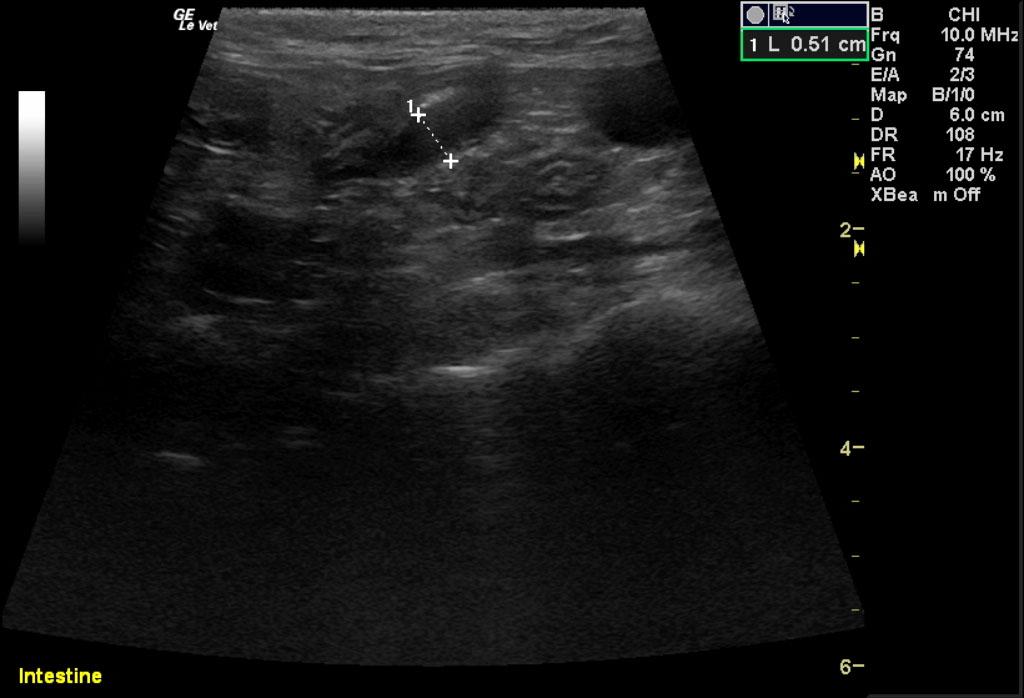

Image 1 & Video 1: The liver was moderately enlarged, rounded in shape having mildly hypoechoic echogenicity with multifocal hypoechoic and cystic nodules throughout. The gallbladder was normal in size, shape, and clean. Images 2-4 & Video 2-4: The left and right kidneys were severely enlarged with mild hydronephrosis in the right kidney. Both kidneys had hyperechoic cortices with large hypoechoic caps surrounding and invading the renal cortices (left kidney cap-7.4 mm in thickness, right kidney cap-13.6 mm in thickness). Image 5 & Video 5: Stomach: mucosal layer is mild/moderately thickened with overall wall thickness measuring 3.8 mm. Images 6: Intestine: there is focal mucosal layer thickening measuring up to 5.1 mm while the rest of the intestinal loops are of normal thickness. Video 6: Colon: the colonic wall appeared thickened at the ileocecolcolic junction. Image 7: Lymph Nodes: Multiple mesenteric lymph nodes were severely enlarged throughout the abdomen. The epigastric LN enlargement is shown in this image in the near field.